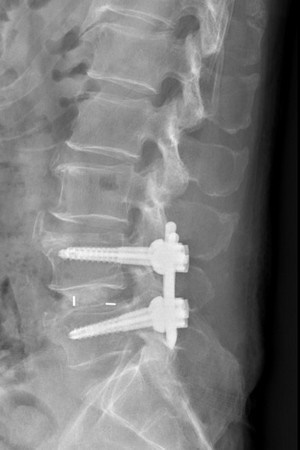

圖:腰椎微創融合手術治療,將鋼釘及支架精準植入,椎間高度與後凸角度恢復良好。